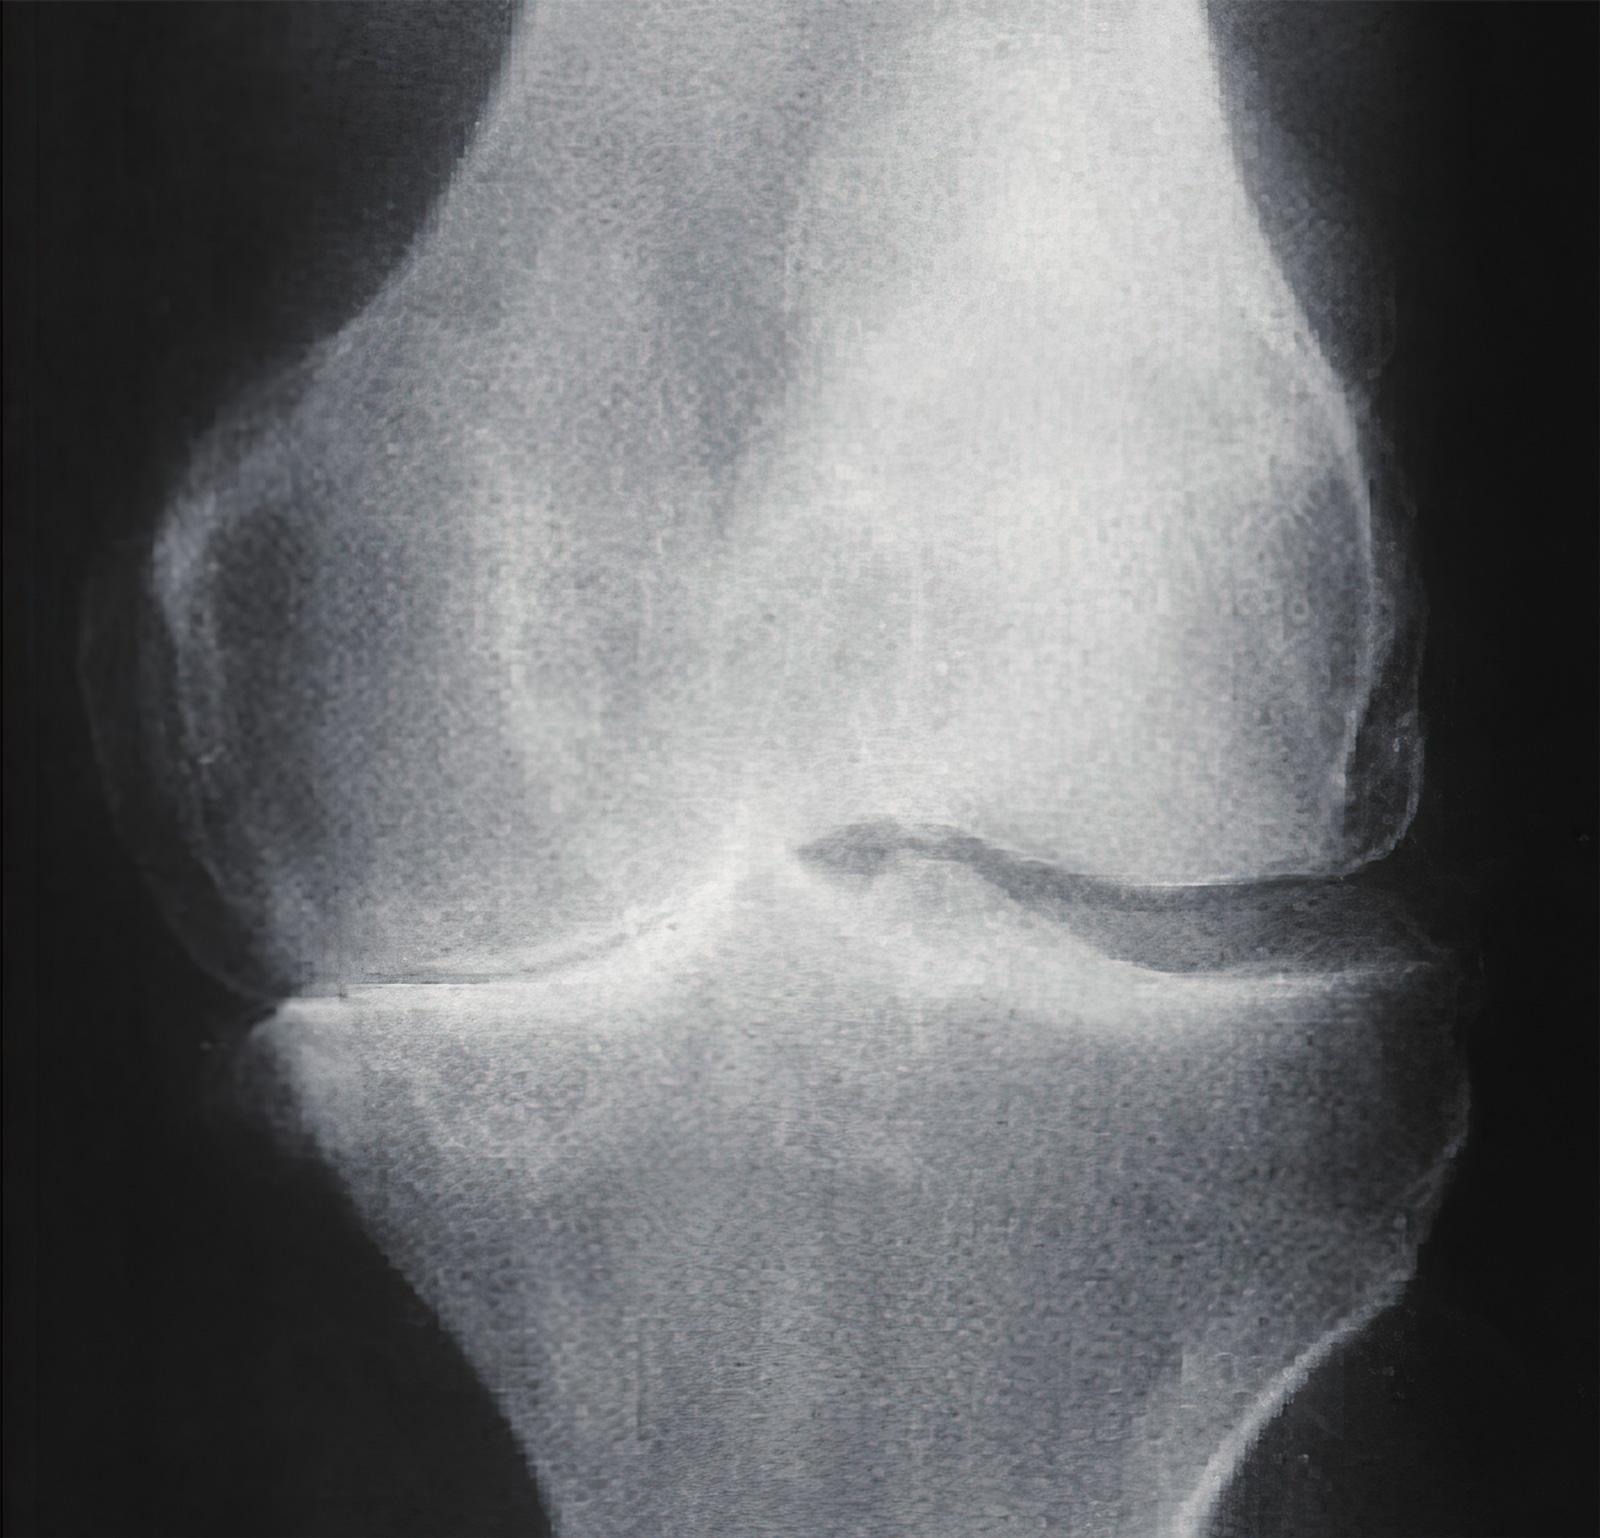

我们知道,膝骨关节炎起始于关节软骨的老化与磨损,继而才会引发骨质增生与滑膜炎症。软骨遭受损伤后,磨损脱落的软骨碎屑就可形成游离体,小如米粒,大如鸽蛋,少则一枚,多则十数枚。这些软骨碎屑充斥在关节腔内,随着膝关节的活动挤压不断游走,所以被称为“关节鼠”。

软骨碎屑可引发滑膜炎症,进而导致滑膜组织增生肥厚,可引起膝关节绞锁疼痛等症状。关节软骨损伤的部位大多还伴有半月板磨损,半月板损伤的程度与软骨损伤的程度成正比,半月板变毛糙、纤维增生,乃至缺损不齐,半月板碎片也是另一种游离体。

- 患者关节间隙严重狭窄,甚至以及骨性强直,镜下操作困难不宜手术;

关节间隙狭窄者不宜关节镜手术